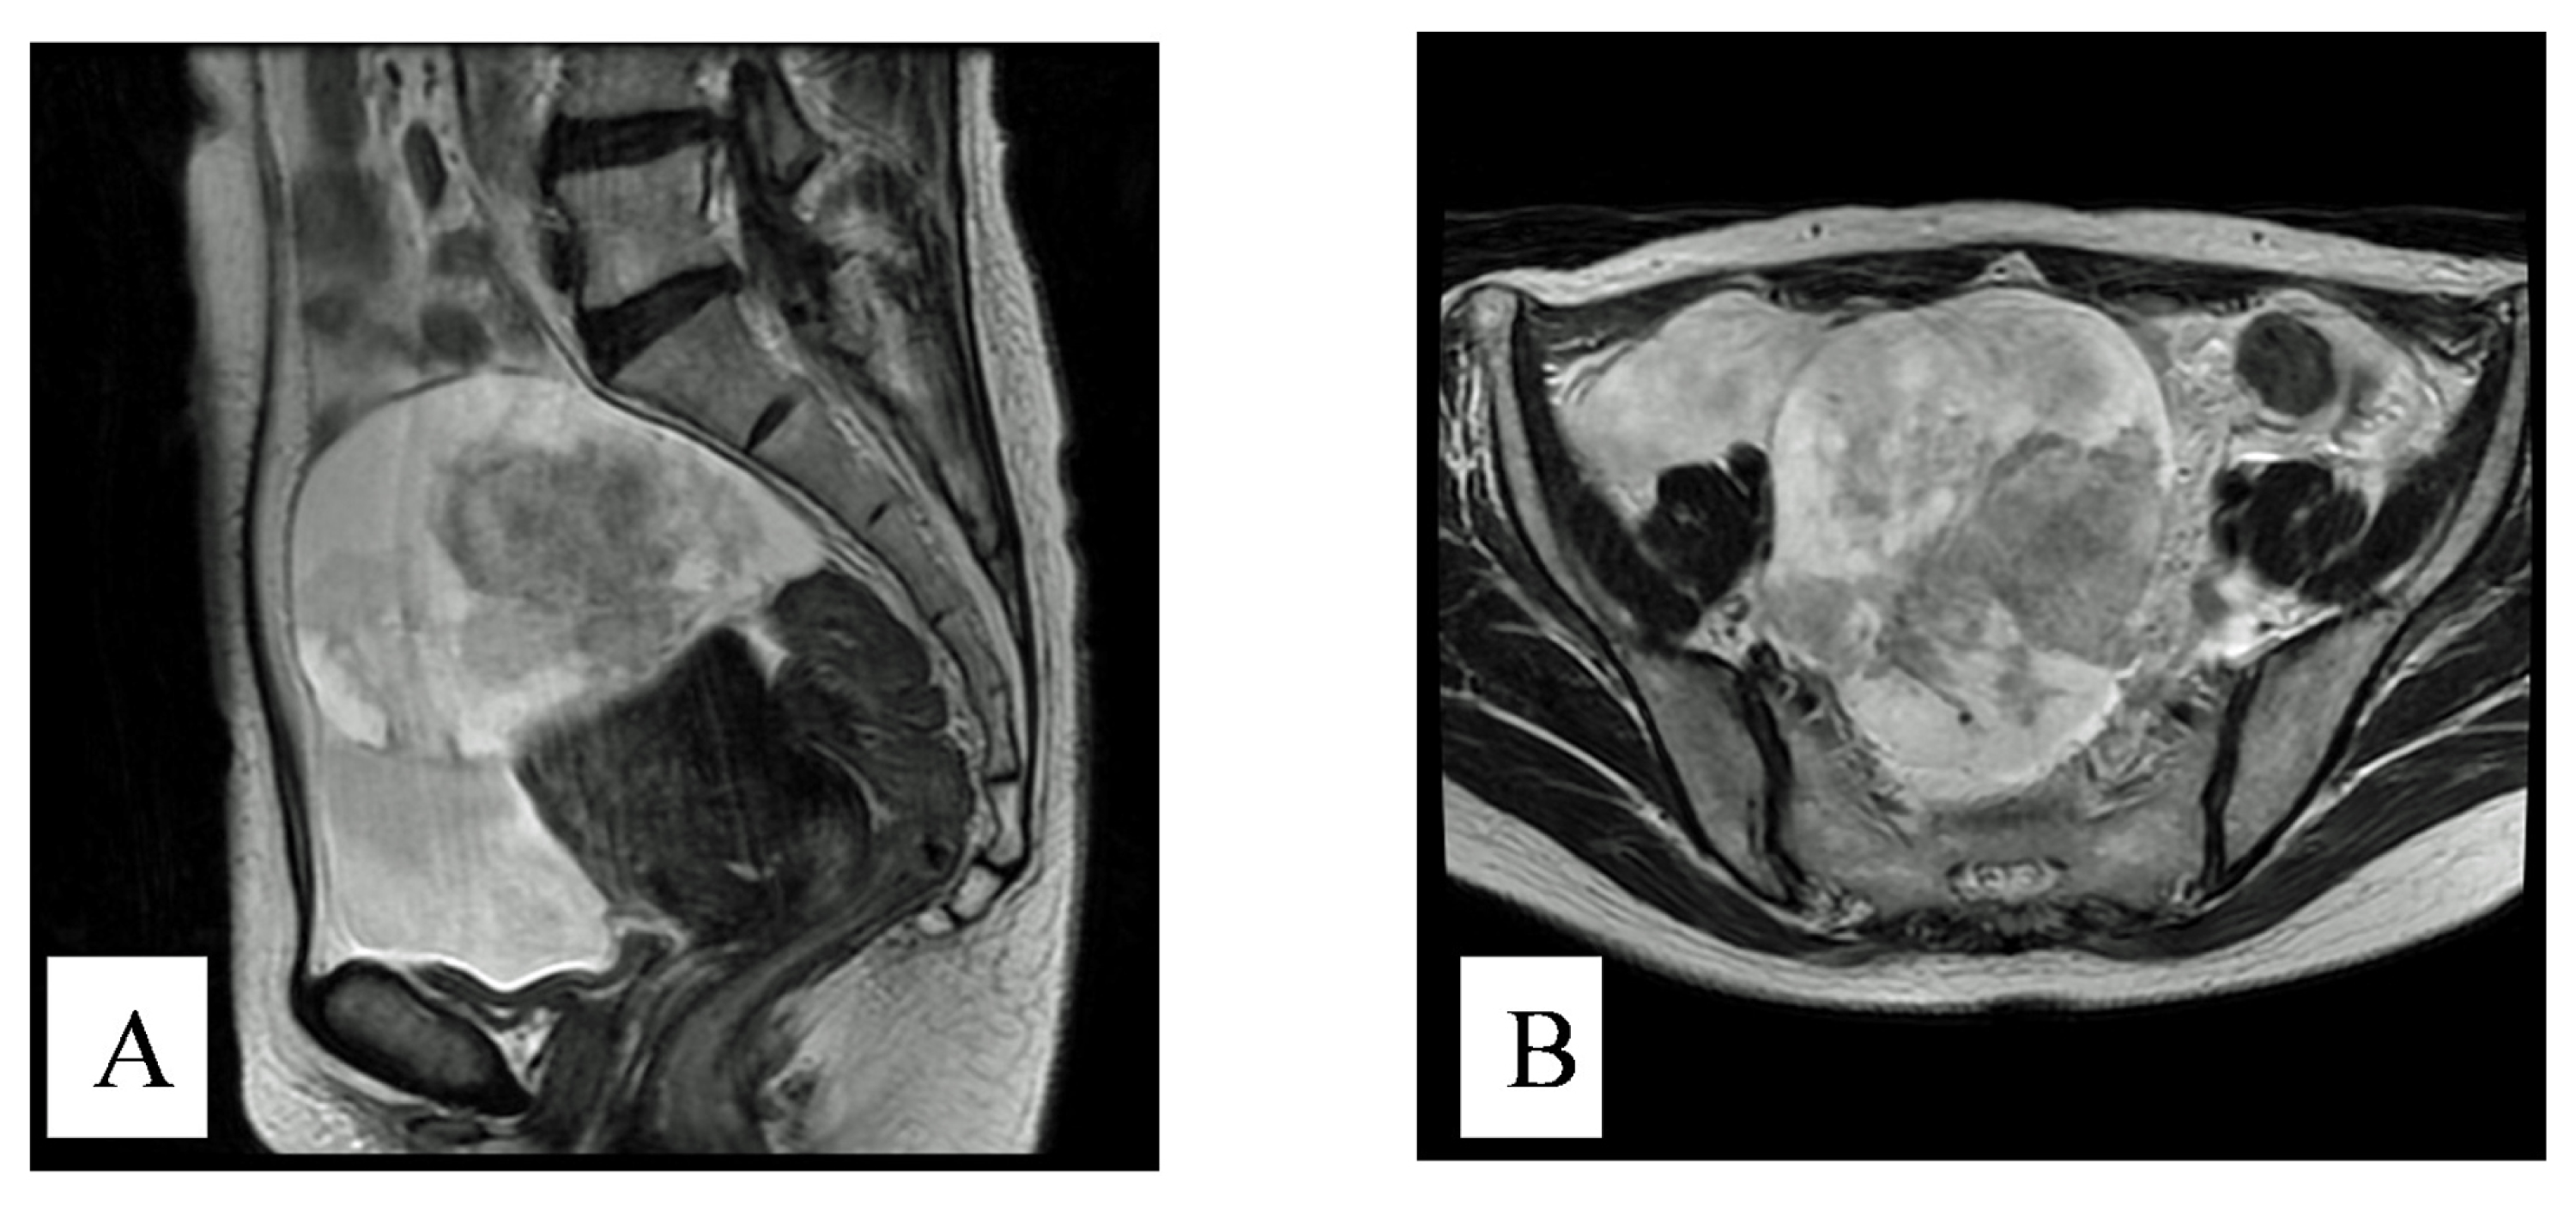

2. Case History